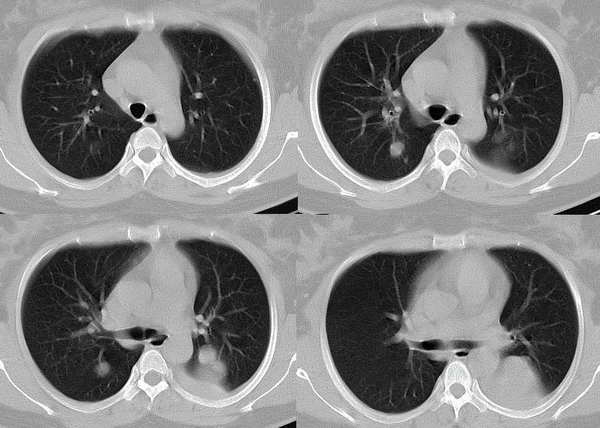

以下是引用wawaquan在2006-2-4 13:32:00的发言:[br]双上叶后段及右下叶多发大小不等圆形高密度影,与血管影相连;左下叶背段呈软组织密度影,边缘膨突,其内见一点状气体密度影,邻近胸膜增厚;纵隔淋巴结不大。[br] 女性,32岁,正哺乳期。近一周发热咳嗽,今晨咳血一次。 [br] 考虑:①双上叶后段及右下叶多发转移瘤,建议查盆腔排除子宫滋养叶细胞肿瘤。[br]②左下叶背段阻塞性炎症可能大。